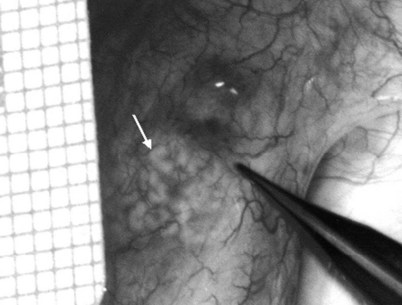

After opening the tunica vaginalis, the epididymis is inspected under the operating microscope. An anastomotic site is selected above the area of suspected obstruction, proximal to any visible sperm granulomas, where dilated epididymal tubules are clearly seen beneath the epididymal tunica (Fig. 22–29). A relatively avascular area is grasped with sharp jeweler’s forceps and the epididymal tunica tented upward. A 3- to 4-mm buttonhole is made in the tunica with microscissors to create a round opening that matches the outer diameter of the previously prepared vas deferens. The epididymal tubules are then gently dissected with a combination of sharp and blunt dissection until dilated loops of tubule are clearly exposed (Fig. 22–30). If the level of obstruction is not clearly delineated after the buttonhole opening is made in the tunic, a 70-µm diameter tapered needle from the 10-0 nylon microsuture is used to puncture the epididymal tubule beginning as distal as possible and fluid is sampled from the puncture site. When sperm are found, the puncture sites are sealed with microbipolar forceps, a new buttonhole is made in the epididymal tunic just proximally, and the tubule is prepared as described previously.

Figure 22–29 An anastomotic site is selected above the area of suspected obstruction, proximal to any visible sperm granulomas, where dilated epididymal tubules are clearly seen beneath the epididymal tunica, as marked by an arrow.